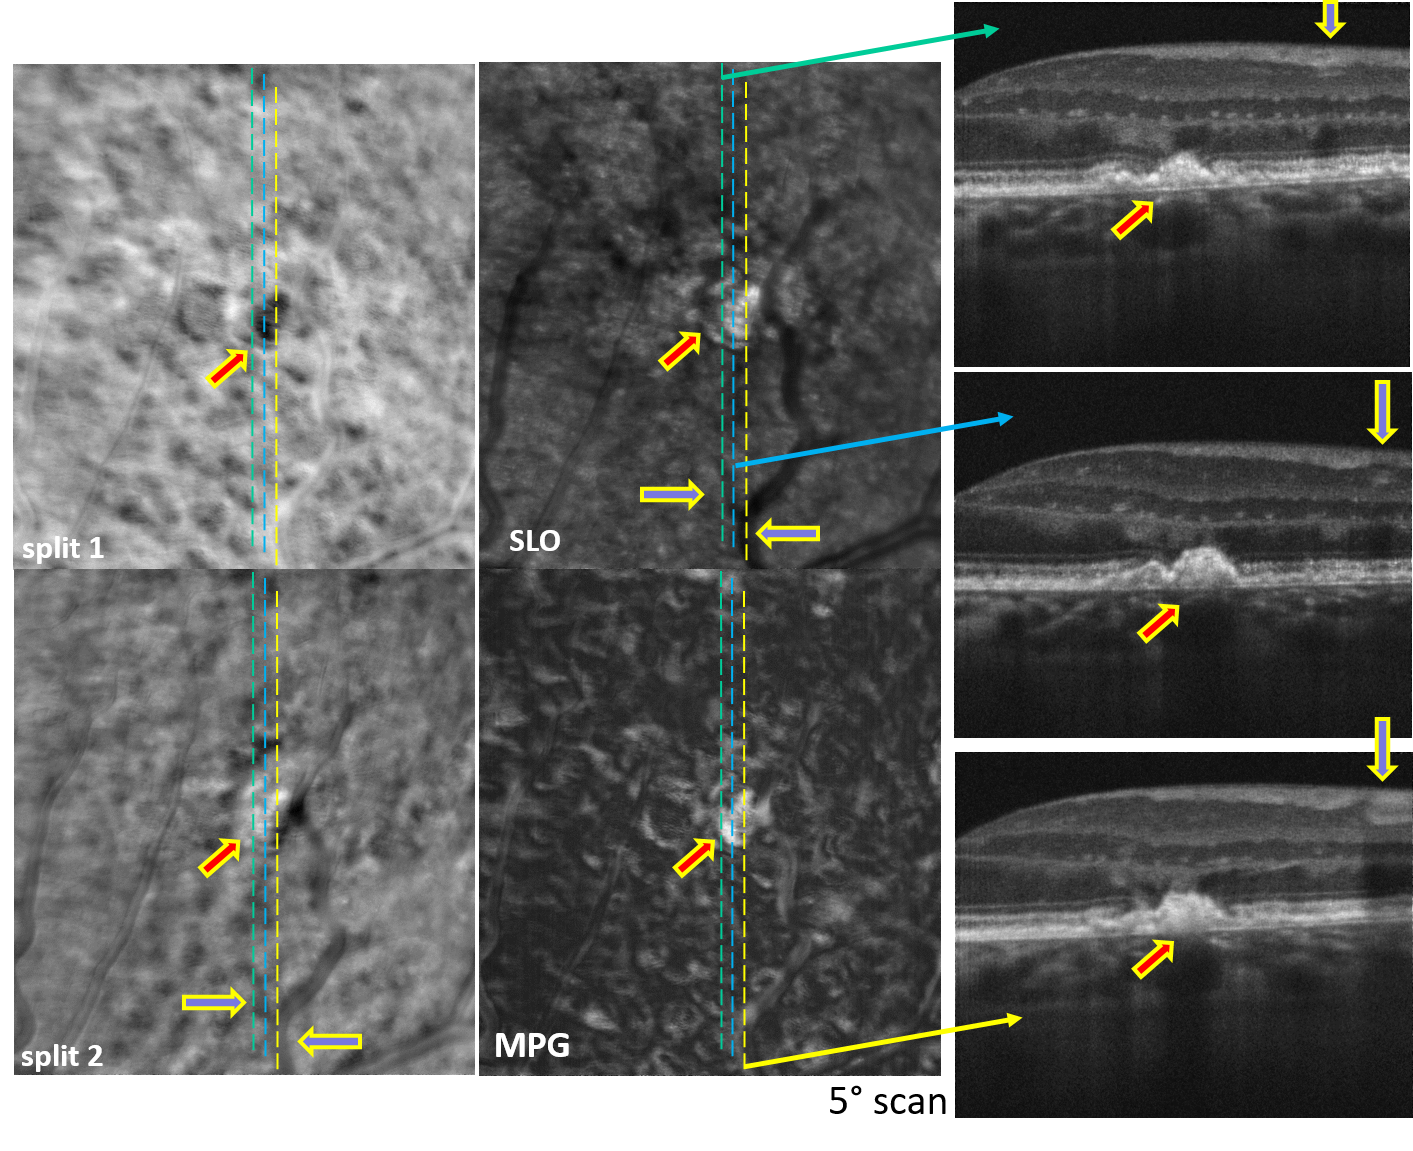

Simultaneous AO-SLO and AO-OCT

Motion Contrast, Phase Gradient, and Simultaneous OCT Images Assist in the Interpretation of Dark-Field Images in Eyes with Retinal Pathology”, Diagnostics, 14(2), 184, (2024)